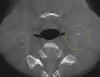

(2.) CBCT axial view of carotid calcifications.

Figure 2

A comprehensive dental exam was performed that included a blood pressure test, an oral cancer screening, intraoral photographs, full mouth radiographs, a periodontal chart, a saliva test, and a CBCT scan. The exam confirmed the presence of active dental decay, periodontitis (ie, stage III, grade B), and areas of calcifications in his carotid artery (Figure 1 through Figure 3).